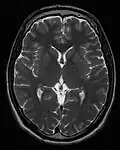

T1 e T2

Cada tecido retorna ao seu estado de equilíbrio após a excitação pelos processos independentes de T1 (spin-tretice) e T2 (spin-spin) de relaxamento. Para criar uma imagem ponderada em T1, a magnetização pode ser recuperada antes de medir o sinal MR, alterando o tempo de repetição (TR). Esta ponderação de imagem é útil para avaliar o córtex cerebral, identificando tecido adiposo, caracterizando lesões focais e, em geral, para obter informações morfológicas, bem como para imagens pós-contraste. Para criar uma imagem ponderada em T2, a magnetização pode decair antes de medir o sinal MR alterando o tempo de eco (TE). Esta ponderação de imagem é útil para detectar edema e inflamação, revelando lesões de substância branca e avaliando a anatomia zonal na próstata e no útero.

A exibição padrão de imagens de MRI é representar características de fluido em imagens em preto e branco, onde diferentes tecidos são os seguintes:

| Sinal | T1-ponderado | T2-ponderado |

|---|---|---|

| Alto | ||

| Intermediário | Matéria cinzenta mais escura que matéria branca | Matéria branca mais escura do que a matéria cinzenta |

| Baixo |

Sequências

Uma sequência de RM (Ressonância Magnética) é uma configuração particular de pulsos de radiofrequência e gradientes, resultando em uma imagem específica.[65] O ponderamento T1 e T2 também podem ser descritos como sequências de RM.

| Grupo | Sequência | Abreviatura | Física | Distinções clínicas principais | Exemplo |

|---|---|---|---|---|---|

| Ponderado em T2 | T2 | Medição da relaxação spin-spin usando TR e TE longos |

|

| |